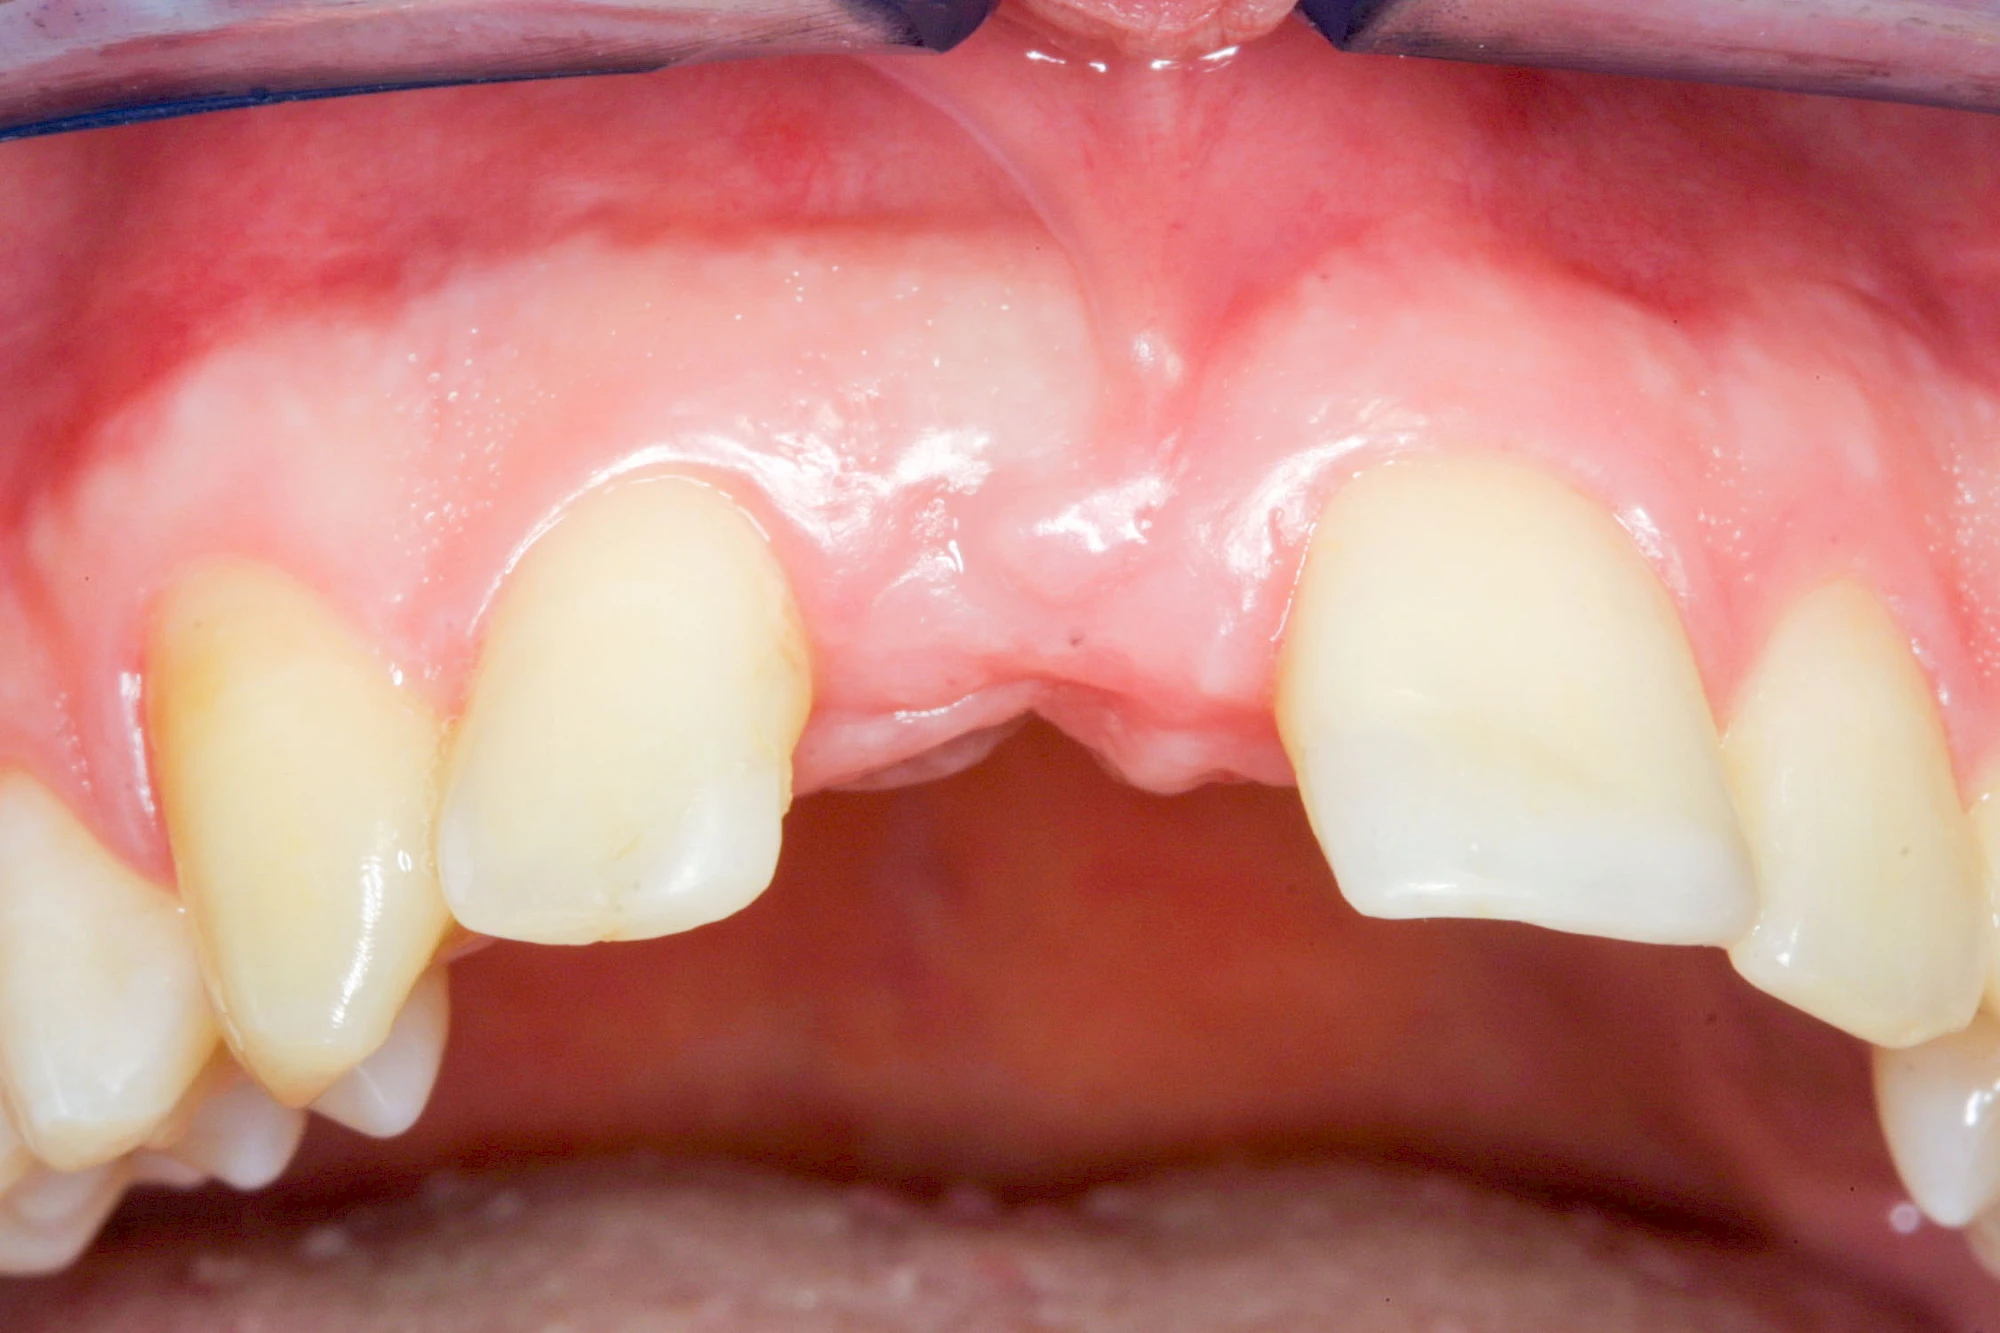

Fehlen einzelne Zähne und die Nachbarzähne sind unbeschadet oder gut zahnärztlich versorgt, werden immer häufiger Implantate gewählt, um die Lücken zu schließen. Auch bei größeren oder verteilten Lücken, wenn keine herausnehmbare Prothese gewünscht ist, werden Implantate für Kronen- bzw. Brückenversorgungen gesetzt. In Einzelfällen entscheiden sich sogar zahnlose Patienten für eine festsitzende Versorgung auf Implantaten.